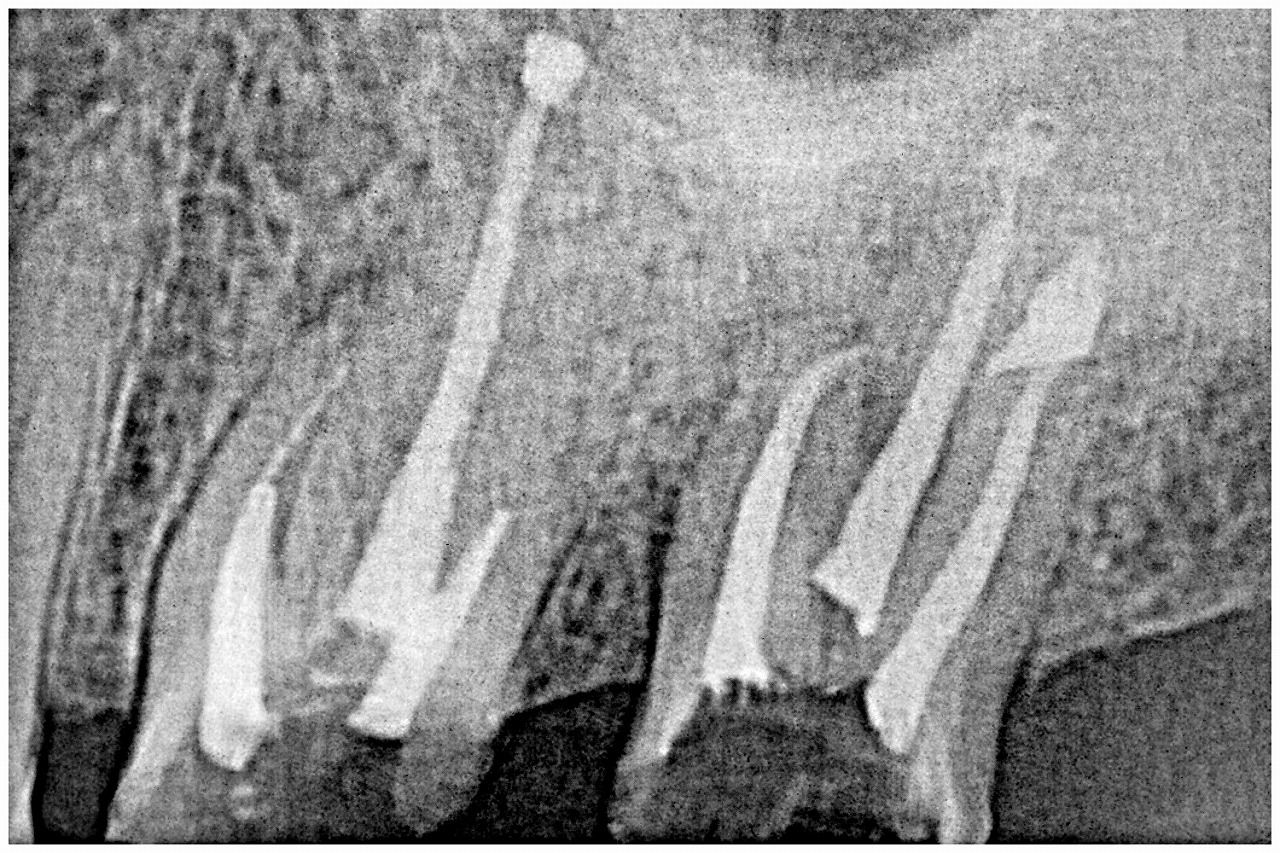

被せを外し

コアを外していきます

根幹治療をおこなっていきました

破折は円も認められましたので最初には抜歯のお話をさせていただきましたが、噛めるので持つまで持たせたいとのこと。